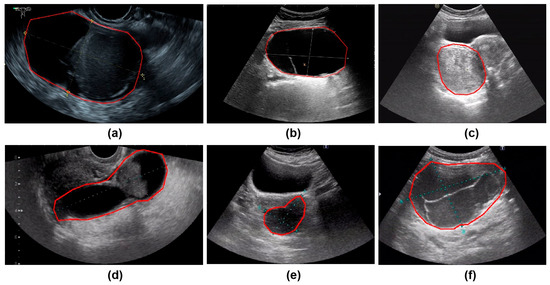

3.6. Interpretability Analysis

Figure 9 presents the results of SHAP (SHapley Additive exPlanations), used to analyze the interpretability of the model predictions. The analysis showed that Confidence, CA125 level, and Diameter were the main contributors to distinguishing between benign and malignant cases, while variables such as menopausal status and age contributed relatively little, consistent with the quantitative results shown in Table 2. In the figure, red points on the right indicate that higher feature values increase the probability of predicting malignancy. Figure 10 presents the visualization of the model’s attention distribution on tumors using the Grad-CAM technique. The highlighted regions indicate the areas that contributed most to the model’s discrimination between malignant and benign features. Through comparative analysis, it was found that the model can focus on highly complex regions of the tumor when predicting malignant lesions, whereas for benign lesions, it can attend to the solid regions.

Figure 10.

The parts circled in red in the image represent the lesions we labelled. (a) A 52-year-old female with high-grade serous carcinoma; (b) a 62-year-old female with borderline mucinous cystadenoma with focal intraepithelial carcinoma; (c) a 50-year-old female with borderline mucinous tumor; (d) a 43-year-old female with mucinous cystadenoma; (e) a 26-year-old female with borderline mucinous tumor; (f) a 76-year-old female with mucinous cystadenoma.